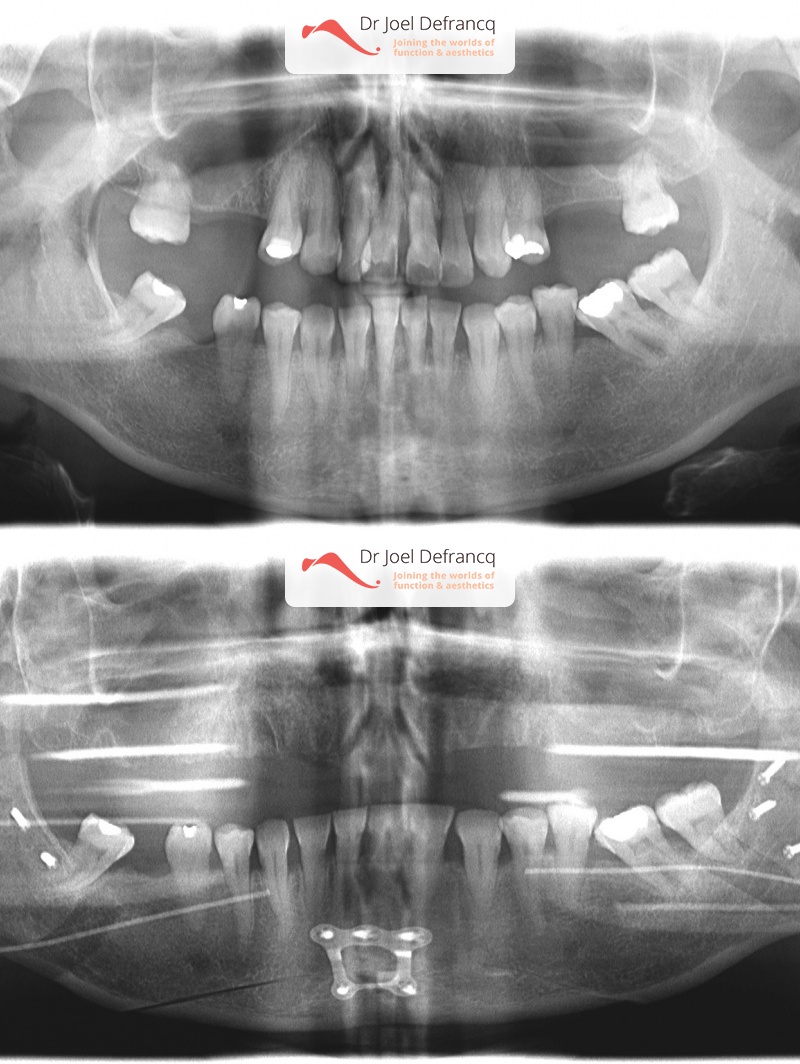

Diana: : Overbeet - diepe beet, smalle bovenkaak - lipofilling

- Te kleine onderkaak (Overbeet)

- Te lange bovenkaak

- Te smalle bovenkaak

- Klasse II divisie 1

- Verlenging onderkaak (BSSO)

- Vertikale verkorting bovenkaak (Le Fort I)

- Kinchirurgie